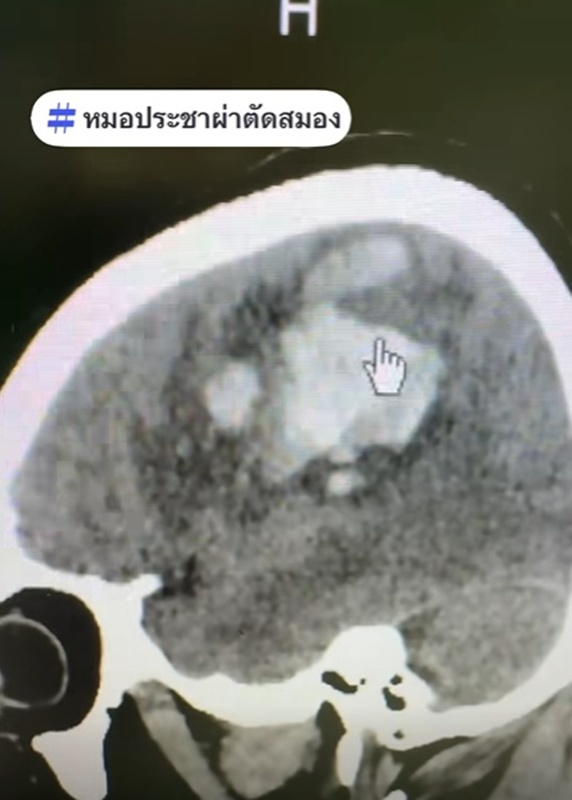

ภาพจาก หมอประชาผ่าตัดสมอง

วันที่ 9 มกราคม 2569 หมอประชาผ่าตัดสมอง เล่าเคส ผู้ป่วยชายวัย 59 ปี ตื่นเช้ามายกแขน-ขาซีกซ้ายไม่ได้ พอสแกนสมองพบจุดขาว ๆ ก้อนใหญ่ นั่นคือ เลือดที่ออกในสมอง จึงรีบผ่าตัดเป็นการด่วน ซึ่งผลการผ่าตัดสำเร็จไปได้ด้วยดี

สำหรับสาเหตุที่ทำให้เส้นเลือดในสมองแตกกรณีนี้คือ ความดันโลหิตสูงและนอนกรน รวมถึงอากาศหนาวจะทำให้คุมความดันโลหิตยากขึ้น เส้นเลือดในสมองจะชอบแตกตอนเช้าตรู่หน้าหนาว หลอดเลือดจะหดตัวจากอากาศที่หนาวเย็น ยิ่งเคสนี้มีนอนกรนและหยุดหายใจตอนหลับ ยิ่งทำให้ความดันโลหิตสูง